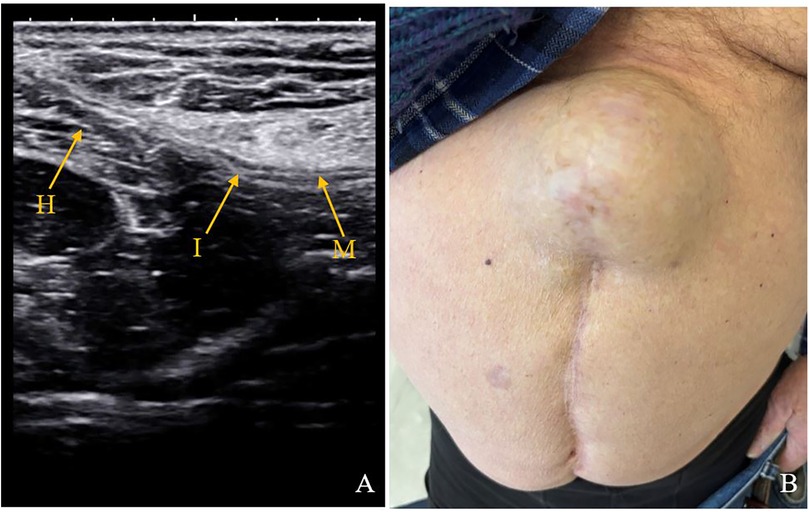

Figure 2

(A) Ultrasound image showing an incisional hernia (H) protruding through the fascial defect (I) with visible mesh (M) beneath. (B) Clinical photograph of the same patient showing a visible bulge along a midline scar consistent with an incisional hernia.

Figure 2. Ultrasound and clinical images of an 83-year-old patient who underwent re-laparotomy on day 13th postoperatively for hemo-peritoneum. (A) Ultrasound image at 23 months post operatively with incisional hernia. (B) Clinical image of a 8 cm incisional hernia. M, mesh; I, mesh interruption; H, hernia.